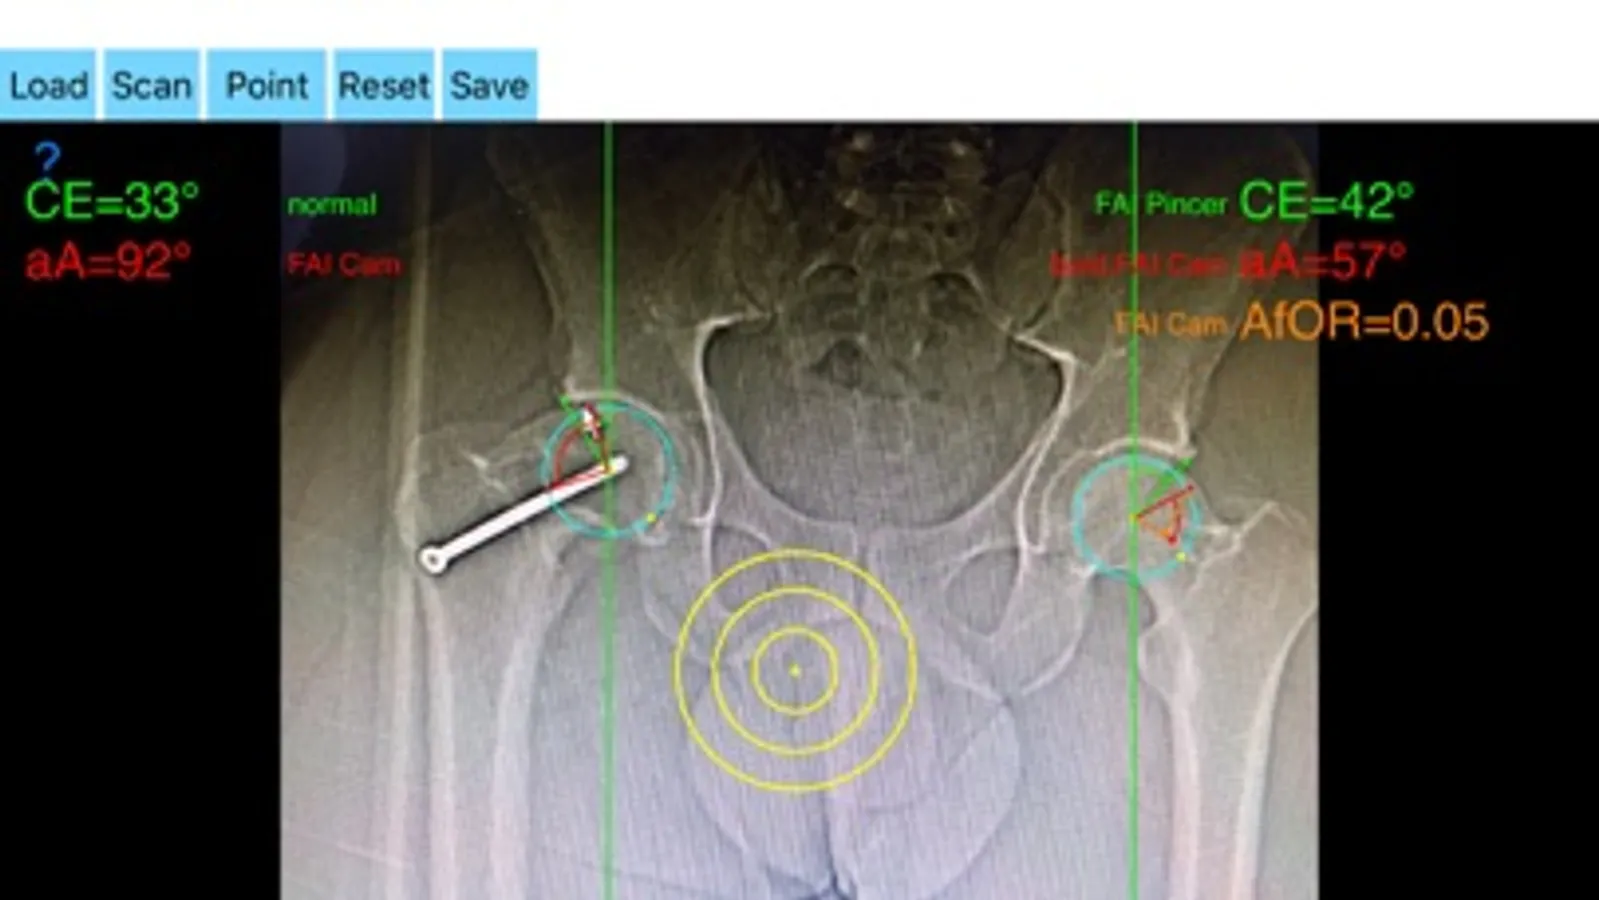

The drawn lines between points, allows app to estimate in radiographs, Center-Edge Angle (CE), α - angle (aA) and the anterior femoral offset ratio (AfOR). The measured values are compared with values from normal reference database. In case the measured angles are beyond the normal range, the hip is categorized as normal, dysplastic, borderline dysplastic hip and the type of femoroacetabular impingement (FAI) deformity namely cam type, pincer type or mixed is printed over the screen accordingly. Measures by the app are not affected by the X-ray projection.